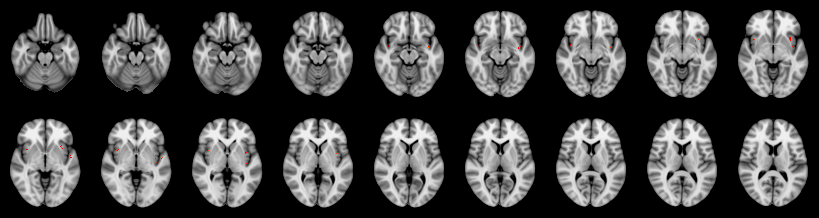

Friston:

IUT/Conjunction/Nichols: